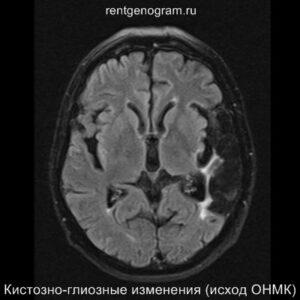

Хроническая фаза (более 6 недель)

В хроническом периоде наблюдаются процессы репарации и пролиферации, что ведет к обратному развитию вазогенного отека и восстановлению ГЭБ, что проявляется полным отсутствием контрастного усиления в зоне поражения. В местах энцефаломаляции формируются ликворные кисты (лакунарный инсульт) или происходят кистозно-глиозные изменения. Также фиксируется снижение кровотока или полная окклюзия артерии в области инфаркта.

Может начать происходить гибель аксонов нейронов, входящих в пирамидный тракт (дегенерация Тюрка-Валлера), создавая выраженную зону глиоза, которая повторяет ход пирамидного тракта. Высокий МР-сигнал на DWI полностью исчезает. Зона кистозно-глиозных изменений может приводить к тракционной дилатации полостей, что вызывает асимметричное растяжение желудка, прилегающего к зоне глиоза (гидроцефалия ex-vacuo).